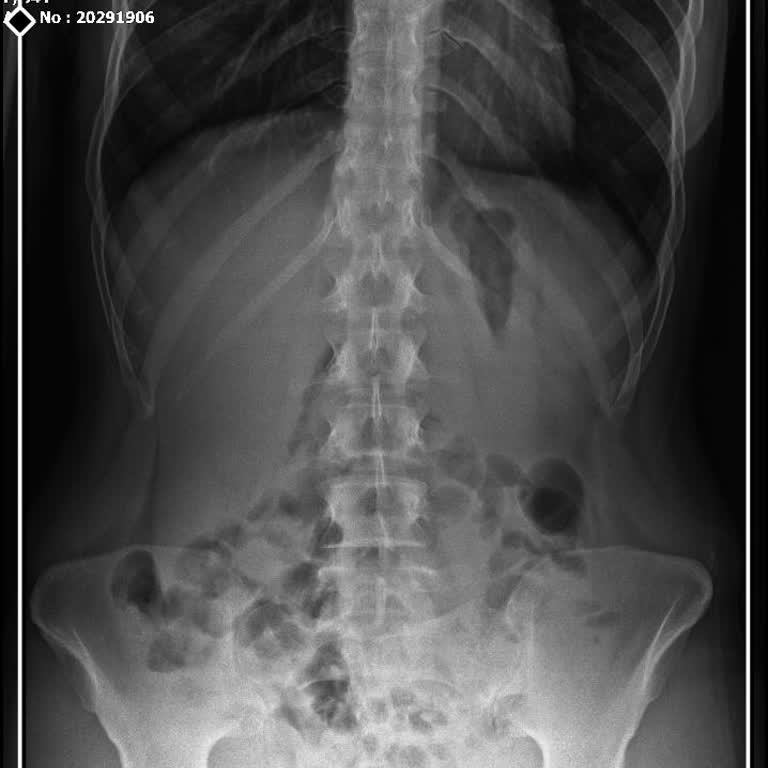

22.11.2024 tarihinde Özel Deva Sağlık Hizmetleri A.Ş.’ye bağlı Antalya Yıldız Medstar Hastanesi’nde doğum hizmeti aldım. Doğum öncesi ve sonrası tüm muayene ve kontrollerim aynı hastanede gerçekleştirildi. Daha sonra benden mevzuata aykırı şekilde fazla ücret tahsil edildiğini tespit ettim ve bu ned...